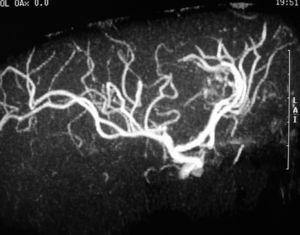

Se realizó una angiorresonancia cerebral en la que se observó una malformación arteriovenosa alimentada por ramas de la arteria cerebral anterior derecha (fig. 2). La angiografía cerebral convencional confirmó los hallazgos de la angiorresonancia. Se desestimaron tanto la embolización selectiva como la cirugía de la malformación arteriovenosa y se realizó radiocirugía. Tres meses más tarde, en una nueva RM se observó un área de hiperseñal en T2 localizada en la región del cuerpo calloso compatible con edema probablemente posradiocirugía (fig. 3). Ante la ausencia de síntomas se adoptó una actitud expectante y se repitió la RM en 3 meses. Esta última fue normal, al igual que los controles realizados cada 6 meses. En una nueva angiografía cerebral convencional realizada 18 meses después de la radiocirugía había desaparecido la malformación arteriovenosa y la paciente se encontraba asintomática.

Figura 2. Angiorresonancia cerebral en la que se observa la presencia de una malformación arteriovenosa alimentada por ramas de la arteria cerebral anterior derecha.